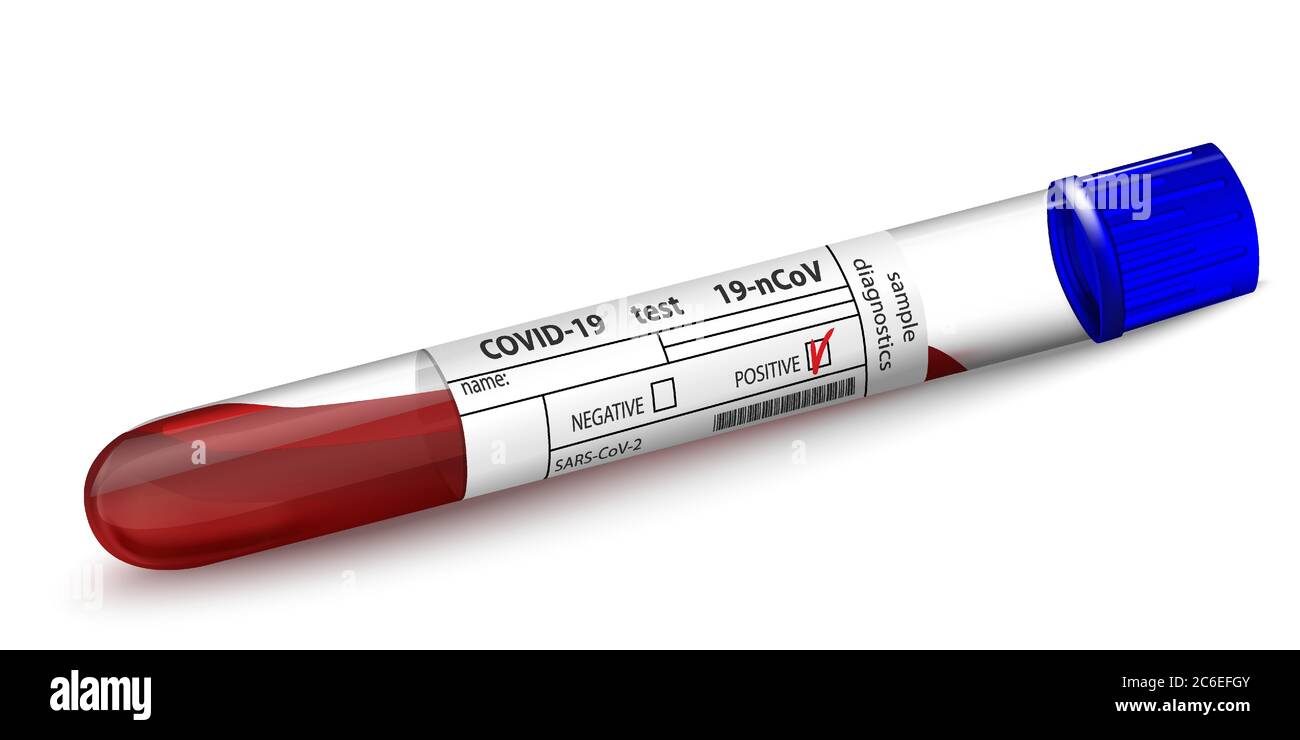

RF2C6ECXB–Tube à essai vierge pour diagnostic virus Covid 19 avec échantillon d'écouvillon Q-Tips. Formulaire de résultat du test sanguin coronavirus 2019-nCoV. 3D vide réaliste isolé

RF2C6EFGY–Tube à essai avec échantillon de sang pour le diagnostic du virus Covid 19. Formulaire de résultat positif pour le résultat du test coronavirus 2019-nCoV. Verre 3d réaliste isolé